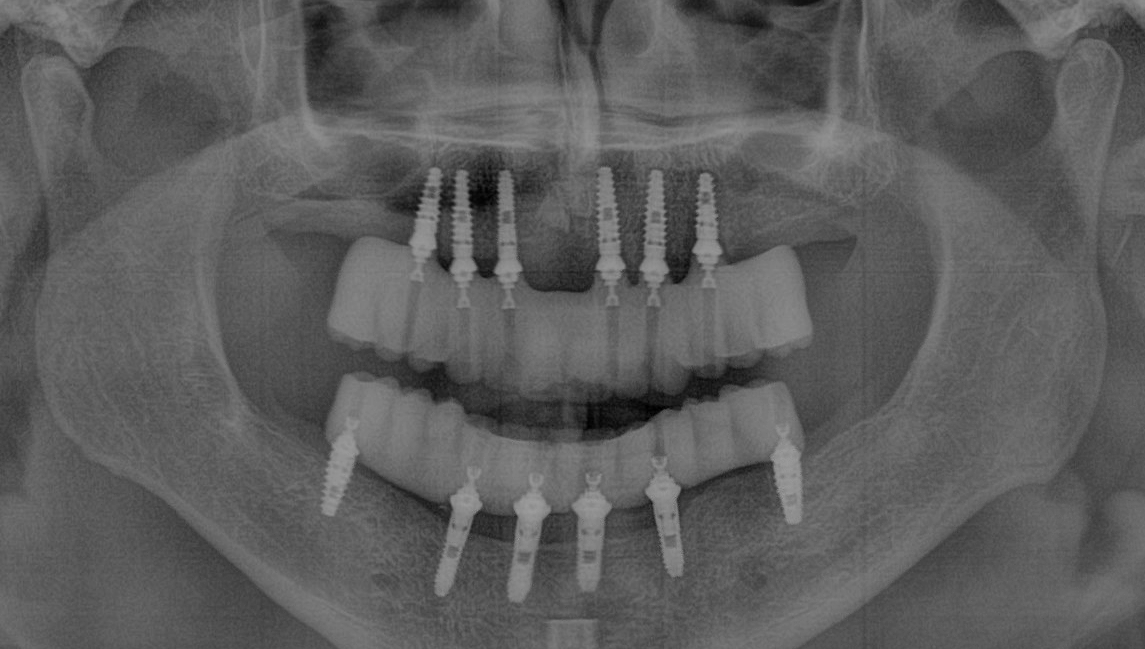

Snap-On Dentures are implant-retained dentures that securely attach to two to four dental implants per arch, providing significantly greater stability than traditional removable dentures. This advanced solution eliminates the need for adhesives and prevents slipping, allowing for improved comfort, function, and confidence when eating and speaking.

• How Do Snap-On Dentures Work?

• Implant Placement – Up to four titanium implants are surgically placed in the jawbone to serve as anchors.

• Healing & Integration – Over three to six months, the implants fuse with the bone to ensure long-term stability.

• Precision Attachments Added – Once healed, specialized connectors are placed on the implants.

• Custom Denture Placement – The denture securely "snaps" onto the implants, providing a secure, comfortable fit with no slipping.

• Snap-On Dentures

Implant-Supported Stability (Approximately 3 Months Total)

• Week 1: 2-4 dental implants are placed into the jawbone.

• Weeks 1-8: Healing and osseointegration period, during which implants fuse with the bone.

• Weeks 9-10: Snap-on attachments are added to the implants.

• Week 12: The custom Snap-On Denture is securely placed for enhanced function and stability.